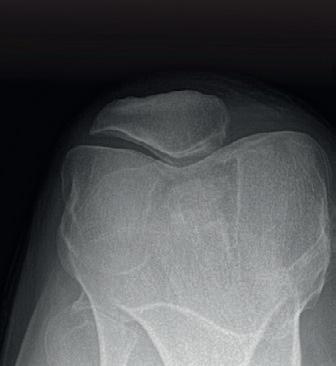

Foto 2 Standaard preoperatief radiografisch bilan. Het betreft hier een eindgradige (cfr Schuss opname) variserende gonarthrose bij onderliggend varus alignement (loodlijn van centrum heupkop naar centrum enkelgewricht loopt door mediaal compartiment op full leg opname). Gezien reeds eindgradige artrose is dit dus geen ideale casus voor osteotomie maar zal eerder voor unicondylaire knieprothese geopteerd worden.

Indicatie wordt gesteld aan de hand van standaard radiografisch bilan. Deze bestaat uit de 4 standaard opnames (face/profiel/ schuss en axiaal) en een Rx full leg opname bilateraal waarop het alignement van de patiënt wordt bepaald (foto 2). Aan de hand van hoekmetingen kan dan bepaald worden waar de afwijking zich bevindt (tibia of femur) en waar de correctie dus dient te gebeuren. Idealiter betreft het een jonge patiënt met een milde tot matige gonartrose volgens classificatie van Kellgren-Lawrence. (foto 3) Resultaten bij een eindgradige (= graad 4) artrose zijn onvoorspelbaar en uitstel naar prothesechirurgie vaak beperkt. Daarom wordt er op dat moment soms beter geopteerd voor een unicondylaire knieprothese.

Foto 3 Kellgren-Lawrence (KL) radiografische classificatie van gonartrose. Pragmatisch werkt men meestal met milde (< 50% vernauwing van gewrichtspleet), matige (>50% vernauwing) of eindgradige (bot op bot) gonartrose.